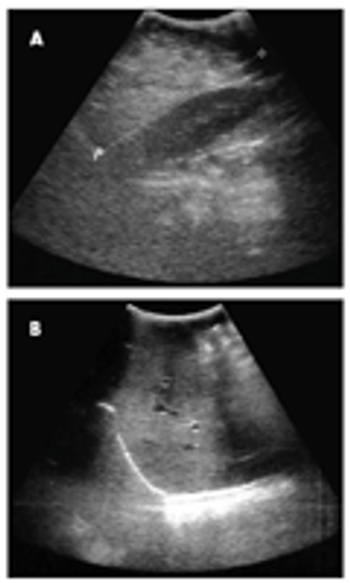

A 6-month-old boy was hospitalized because of fever and suspected central line sepsis. He had been receiving total parenteral nutrition (TPN) since shortly after birth following a small-bowel resection, which was performed to repair a midgut volvulus. Abdominal ultrasonographic findings after the procedure were normal. The infant was born at term after an uneventful pregnancy and delivery. Alkaline phosphatase and γ-glutamyl transpeptidase levels were elevated, without hyperbilirubinemia. An ultrasonogram showed hyperhomogeneous and nonhomogeneous echogenicities of the liver, consistent with fatty changes and fibrosis.